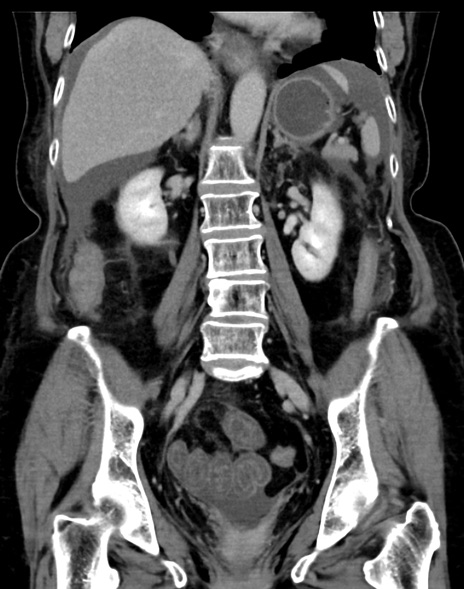

症例13 CT(冠状断像)1日半後